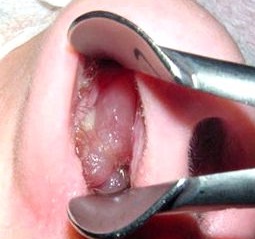

Полипы в носу представляют собой доброкачественные образования, которые способны вызывать ряд неприятных симптомов. Пациенты часто жалуются на затрудненное дыхание, постоянную заложенность носа и снижение обоняния. Некоторые из них отмечают, что полипы могут приводить к частым синуситам и головным болям. На фотографиях полипов можно увидеть их характерные черты: они выглядят как мягкие, желтоватые или прозрачные образования на слизистой оболочке носа.

- 1) Полипотомия – механическое удаление полипов с помощью специального медицинского инструмента – крючка Ланге, напоминающего по внешнему виду петлю. Операция проводится после введения в область полипа раствора анестетика. Согласно статистике рецидив заболевания после данного вмешательства встречается у каждого второго пациента;

- 2) Эндоскопический метод удаления полипов предусматривает введение в полость носа специального прибора – эндоскопа. С его помощью врач рассматривает изображение на мониторе и судит о патологическом процессе и дальнейших манипуляциях. Разновидностью эндоскопического метода является оперативное вмешательство с применением специального прибора под названием шейвер. С его помощью полип удаляется с максимальной точностью до тканей без патологии. Результатом операции является сокращение восстановительного периода. Это один из немногих методов, при котором вероятность возникновения полипов повторно минимальна;

- 3) Лазеротерапия осуществляется после подготовки пациента (обезболивания) в амбулаторных условиях. Данная операция проходит с минимальным кровотечением и воспалением тканей, так как луч сразу запаивает сосуды и обеззараживает.